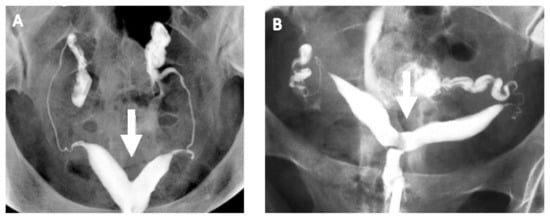

4.1. Hysterosalpingogram

HSG helps in evaluating the uterine cavity but a definitive diagnosis of CUA requires evaluation of the external uterine contour, which is poorly defined by HSG. However, HSG, a commonly employed test to assess tubal patency as a part of fertility investigation, is a good screening test for CUAs. The angle of divergence of the uterine horns of less than 75° and more than 105° has been suggested to diagnose the septate and bicornuate uteri, respectively (Figure 3) [12]. However, the majority of these anomalies overlap and angles between the horns fall within this range. Furthermore, HSG cannot reliably differentiate between septate and bicornuate uteri because of its limitation in evaluating the external uterine contour. In addition, HSG can visualise the uterine cavity only if it communicates with the cervix and cases of non-communicating rudimentary uterine horn may be missed.

Figure 3. Hysterosalpingogram showing acute angle in a septate uterus (A) and wider angle in a bicornuate uterus (B).